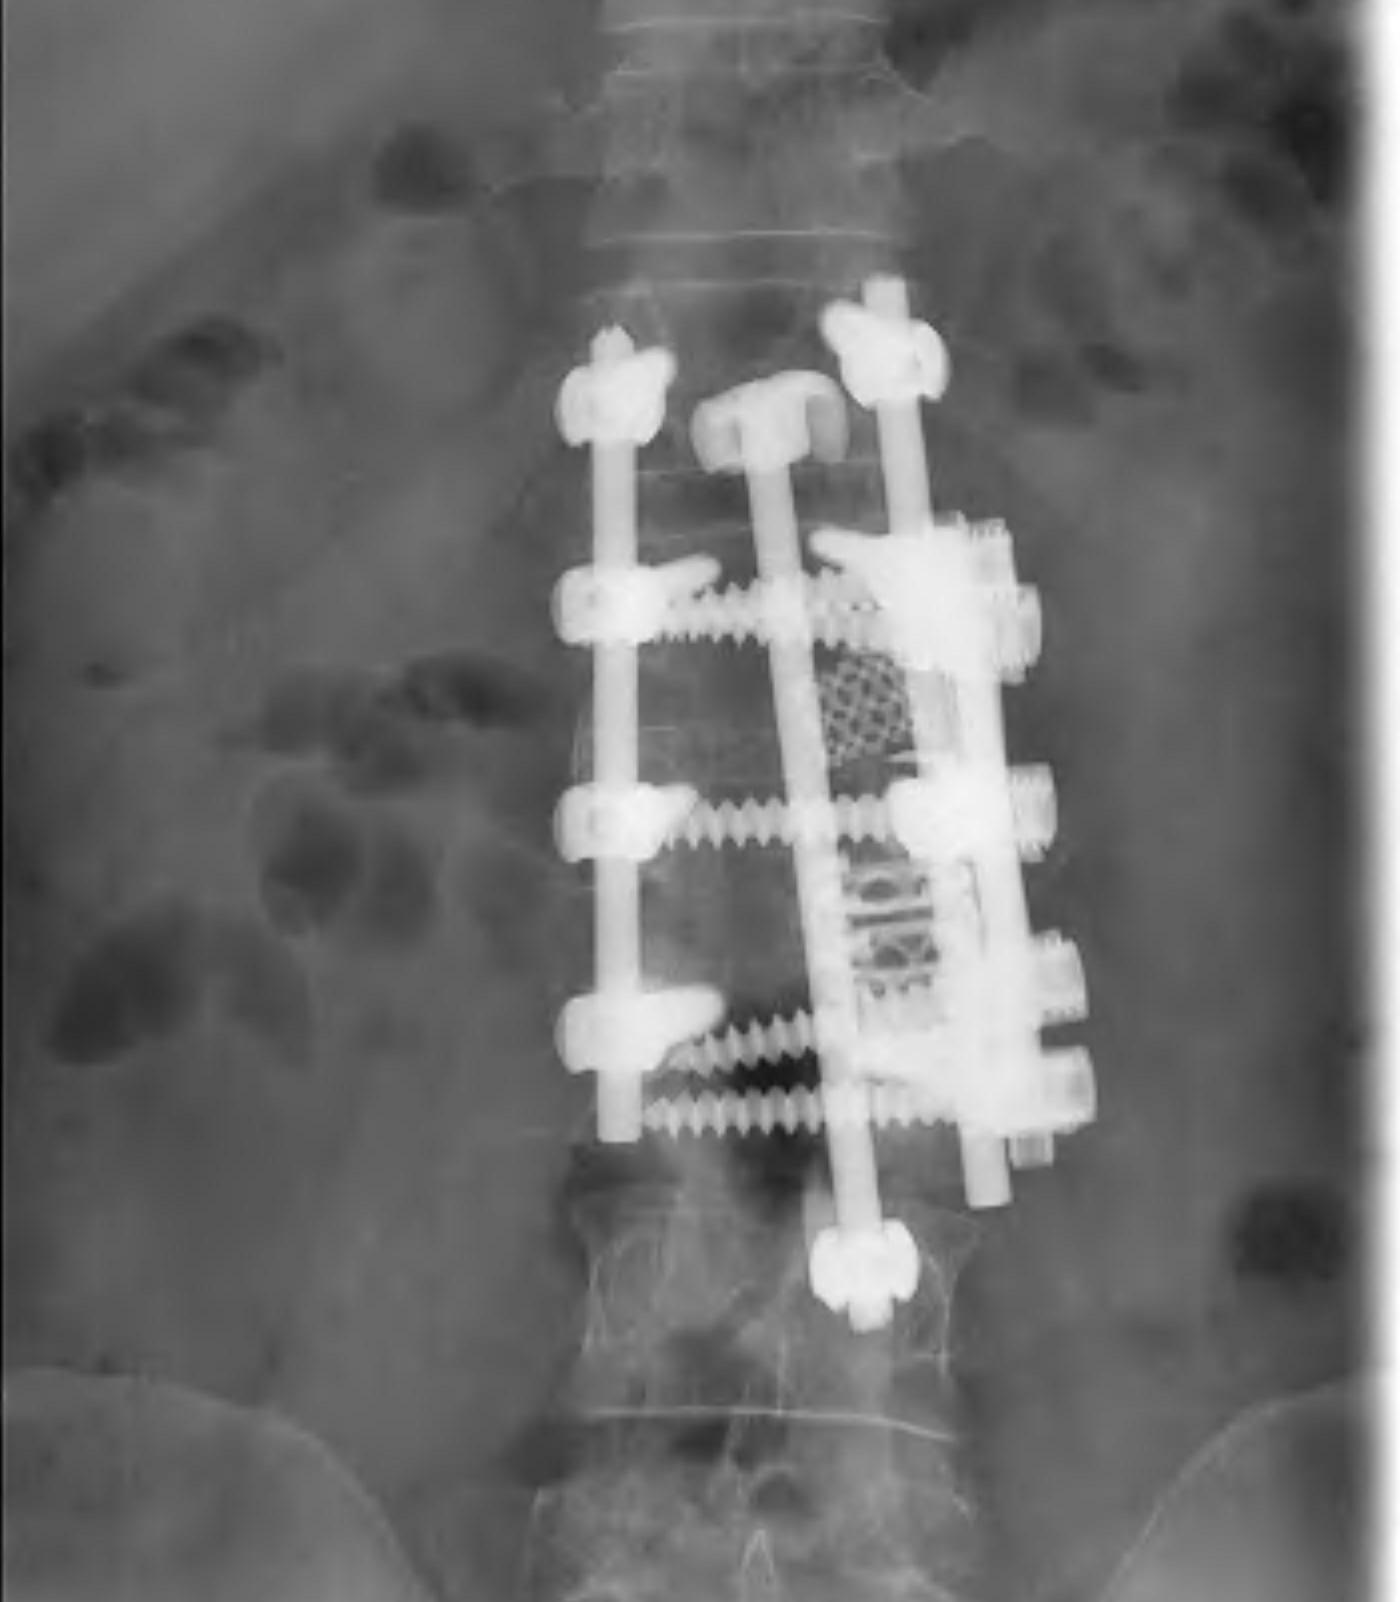

Anterior corpectomy and strut graft

Indication

- decompression of retropulsed fragments in patient with neurology

Technique

- approach as per level

- thoracoabdominal for T11 - L1

- thoracotomy for T2 - T10

- remove disc above and below and remove vertebral body

- remove fragments / need to know if 1 or 2

- screws in vertebral body above and below

- 2 screws in a lateral plane

- insert fibular strut allograft / titanium cage

- augment with cage

Posterior instrumentation